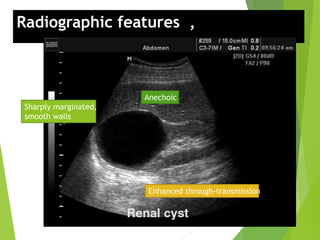

Radiographic features , US:

Anechoic

Enhanced through-transmission

Sharply marginated,

smooth walls

Radiographic features ,US: Anechoic Enhanced through-transmission Sharply marginated, smooth walls